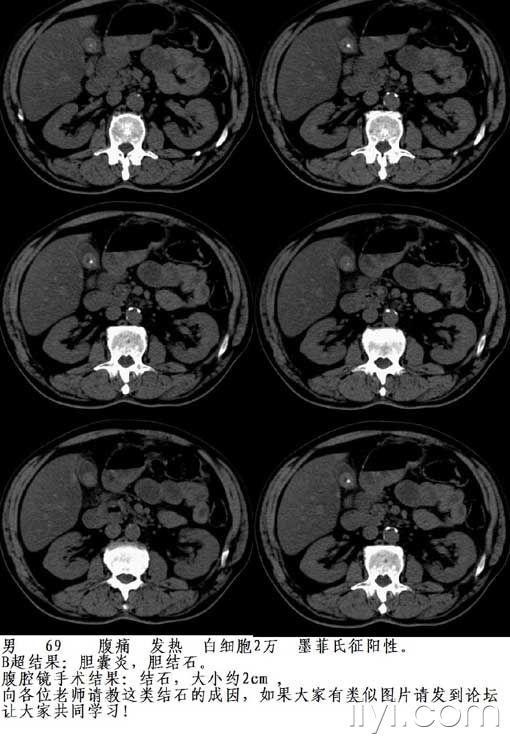

【共享】一例腹腔镜证实的特殊类型胆囊结石,请大家指教(如有类似图片

图片尺寸510x743